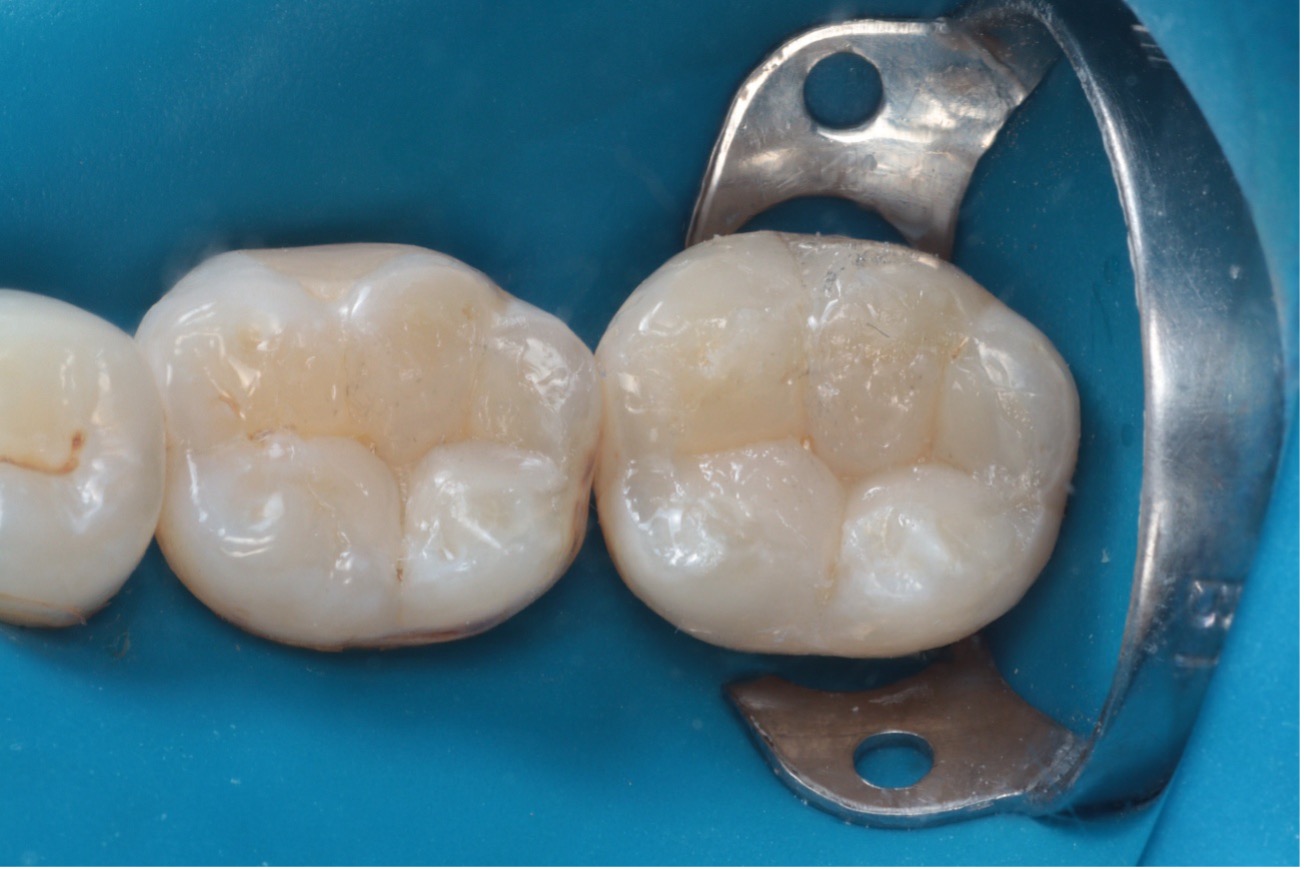

O resultado clínico demonstrou excelente integração estética, funcionalidade adequada e satisfação por parte da paciente (Figura 13).

Figura 13 – Resultado final